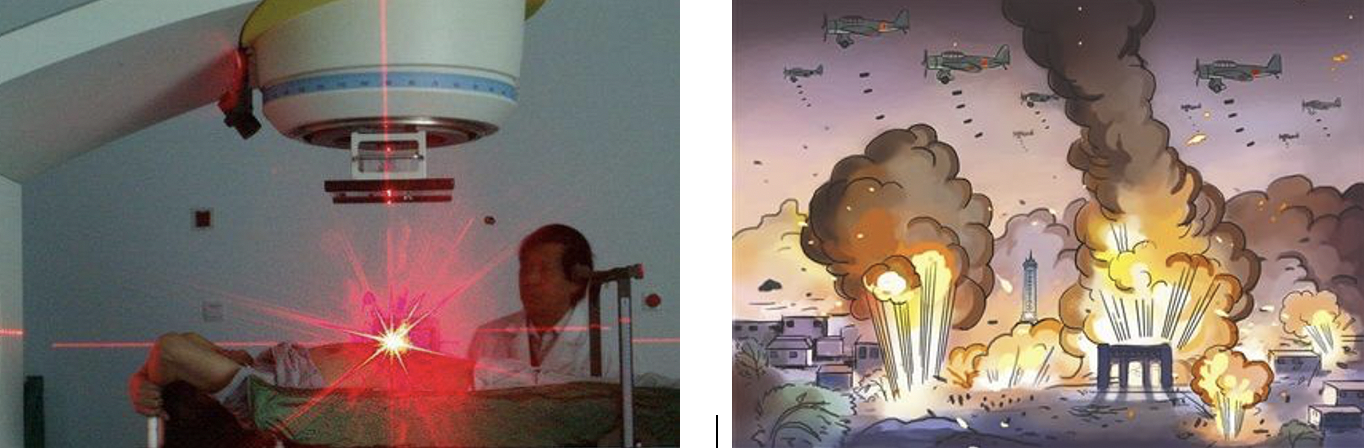

如果将传统放疗比作对目标进行空中战略性轰炸的话,那么碘粒子植入放疗就好比将炸药输送到目标内部进行精准定向爆破打击。

传统放疗

粒子植入